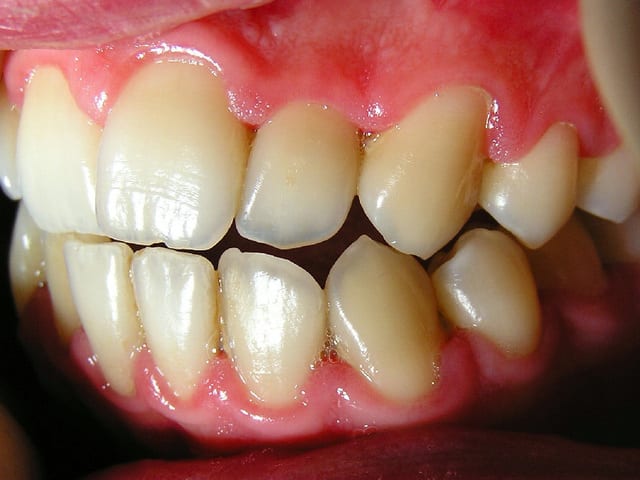

J'ai ressorti les photos prises initialement:

22/06/2005 à 02h01